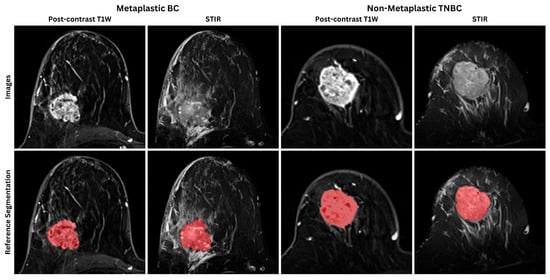

2.7. Ground-Truth Annotations and Inter-Observer Agreement